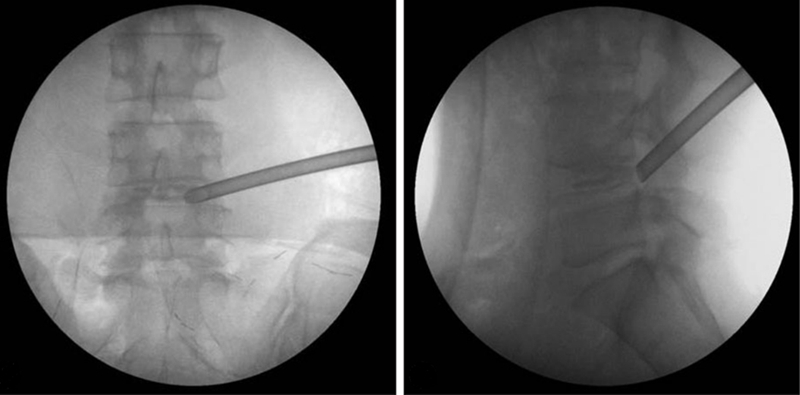

由于PTED技术学习曲线陡峭,早期手术出现神经损伤的并发症更高。在术前应结合每位患者的病情进行评估,决定术中具体的穿刺方式和路径;在穿刺置管过程中应小心谨慎,尤其是需要椎间孔成形操作的患者应在操作过程中时刻进行影像学透视监测,术中应仔细辨别组织解剖结构,特别是安全三角区,在减压取出髓核时询问患者有无下肢疼痛,防止暴力操作。